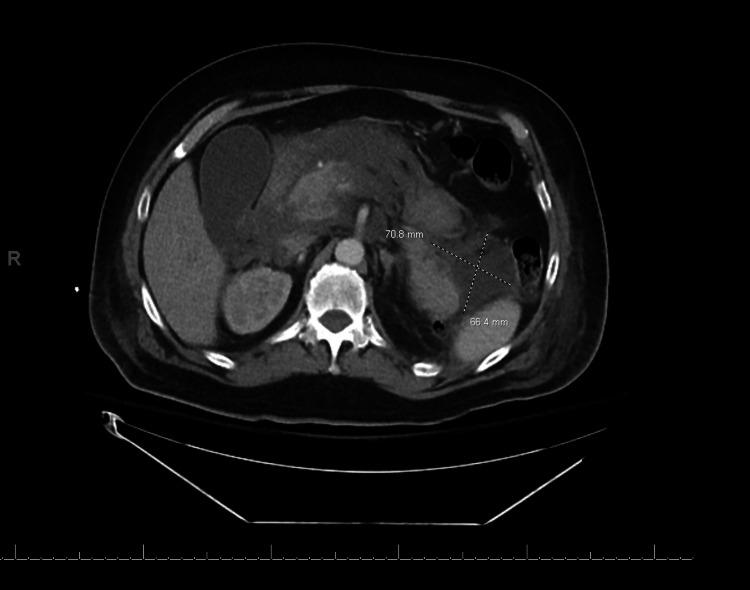

坏死性胰腺炎:是否抗凝?

Necrotizing Pancreatitis: To Anticoagulate or Not to Anticoagulate?

Necrotizing pancreatitis is an inflammatory process that poses a strong risk of systemic venous thromboembolism. However, it is often challenging to opt for systemic anticoagulation since the disease is also associated with an increased risk of hemorrhage. Given these opposing complications, a risk versus benefit analysis has to be employed in the management of necrotizing pancreatitis on a case-by-case basis. We discuss a case where the team was faced with a dilemma regarding anticoagulation in a patient with newly developed atrial fibrillation in the setting of necrotizing pancreatitis. We found that there is a lack of guidelines that address the time of initiation and the type of systemic anticoagulation that should be administered in such patients.

摘要